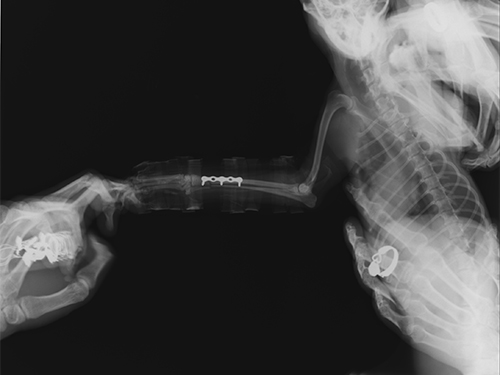

图2:手术前右前肢侧位图